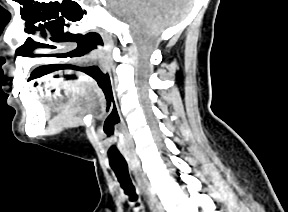

Оптимальным методом обследования гортани и голосовых связок является мультиспиральная компьютерная томография. Метод позволяет подробно визуализировать состояние данной анатомической области и выявить патологические изменения, которые незаметны при ларингоскопии (визуальный осмотр гортани с помощью специальных инструментов), проведении УЗИ и обычной рентгенографии.

Компьютерная томография особенно полезна для оценки состояния хрящей гортани, которые лучше всего визуализируются с помощью данного исследования. В частности, мультиспиральная КТ позволяет выявить распространение рака гортани в ткань щитовидного хряща и другие окружающие структуры.

На полученных снимках можно оценить состояние всех структурных элементов гортани, голосовых складок, хрящей, а также лимфатических узлов, сосудов и шейных позвонков на исследуемом уровне. Инновационные возможности аппарата позволяют построить 3D-модель зоны исследования, которая дает наглядную картину пространственного расположения органов, что бывает особенно важно при планировании хирургических операций.